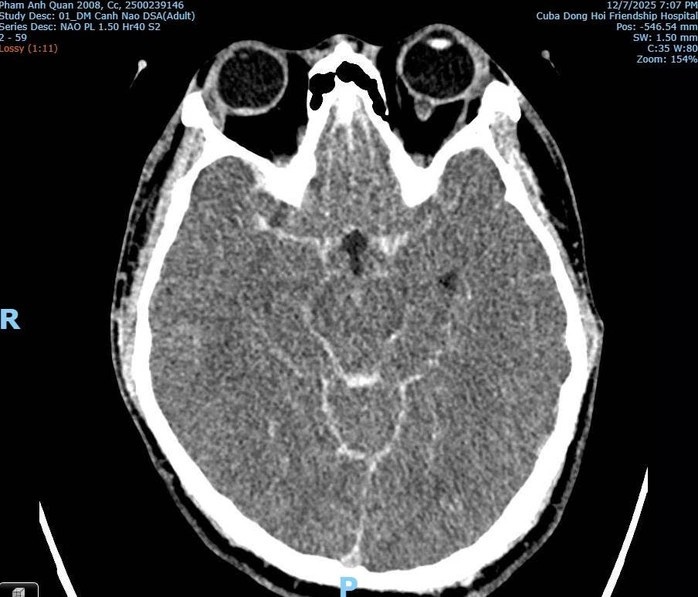

Hình ảnh thể hiện co thắt mạch máu não do xuất huyết não và vỡ phình mạch.

Trao đổi với phóng viên, bác sĩ Nguyễn Đức Hùng, Trưởng khoa Chẩn đoán hình ảnh cho biết, sau khi xem kỹ video vụ việc và phân tích hình ảnh CT Scan vùng cổ - não của bệnh nhân, nhiều khả năng Q. tử vong do vỡ phình mạch máu não bẩm sinh, một dị dạng mạch não sâu và thường chỉ được phát hiện qua chẩn đoán chuyên sâu.

Theo bác sĩ Hùng, hình ảnh chẩn đoán không ghi nhận tổn thương xương cột sống cổ, tổn thương hộp sọ, tổn thương não do lực đánh trực tiếp. Ngược lại, chỉ thấy xuất huyết dưới nhện, phù não lan tỏa, dấu hiệu điển hình của vỡ phình mạch bẩm sinh, không phải chấn thương do bị đánh.

Xuất huyết dưới nhện do vỡ phình mạch máu não của bệnh nhân Q.